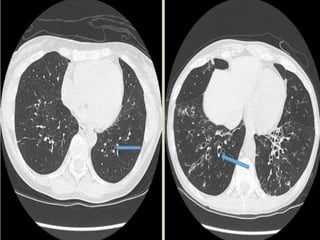

Focal bronchiectasis (idiopathic) in left lower lobe (arrow).

A

B